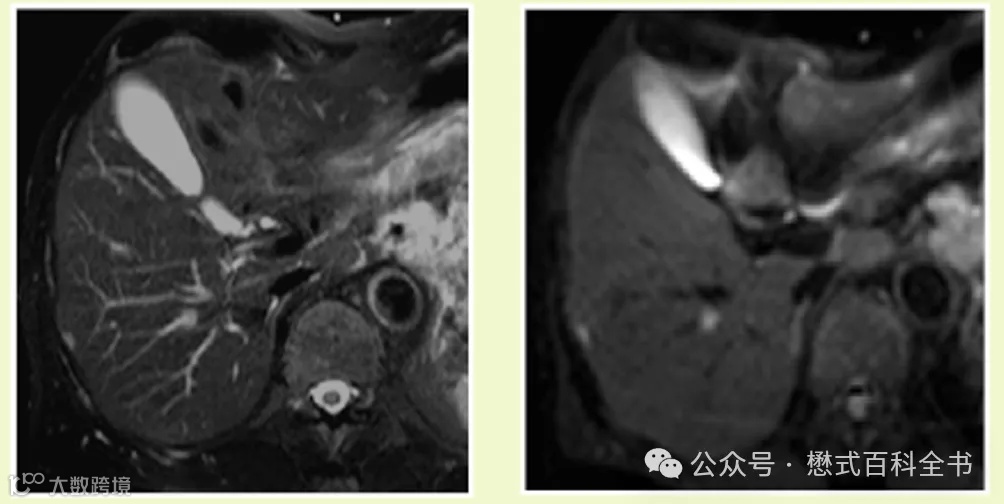

肝脏扫描,常规脂肪抑制的T2WI序列诊断效能还是挺高的,一般来讲不会去省略它。即使这个肝脏扫描序列有全套,包括动态增强扫描。也很少有医院省略一个T2WI。

图8:肝脏扫描DWI:b=0和b=800(屏气扫描,19s)

上图可以发现,常规的肝脏T2WI-fs,虽然图像信噪比高,空间分辨率也不错,但是肝脏的脉管系统是高信号。而采用了低b值的DWI,抑制了肝脏内脉管信号,对于一些小病变的检出就更敏感了。